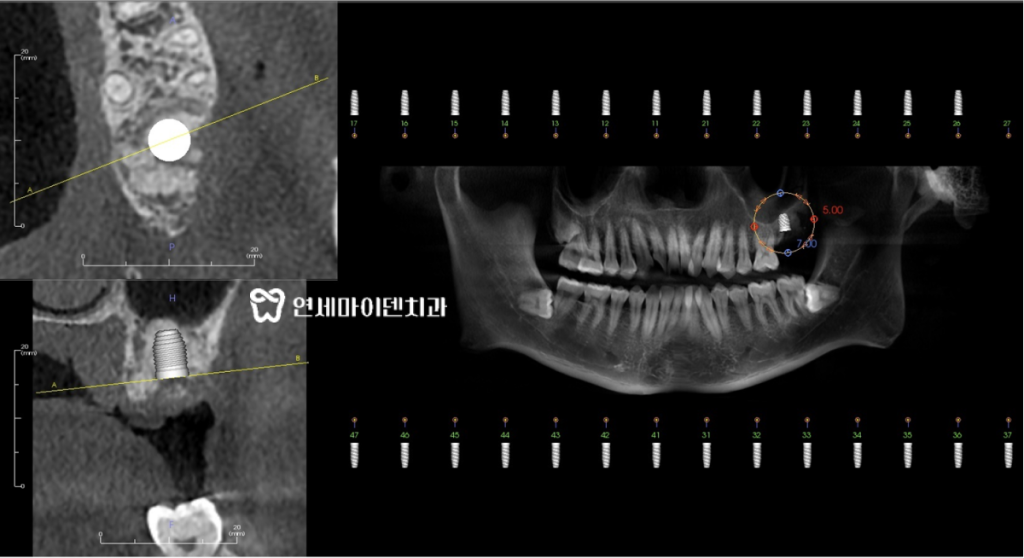

먼저 엑스레이와 CT 촬영을 진행합니다.검사를 통해 신경관의 위치와 치아 주변 뼈 상태를

꼼꼼하게 확인합니다.특히, 아래턱에 임플란트를 식립할 때에는

신경관이 지나가는 경로를 꼭 정확하게 파악해야 합니다.

심한 통증을 느낄수 있어서 매우 섬세한 작업이 필요합니다.이 환자분의 경우에도 CT 촬영을 통해 신경관의 위치를 정확하게 파악했고

이를 토대로 임플란트를 안전하게 심을 수 있는 위치와

정확한 각도를 설정해주었습니다.임플란트 수술 전 치과의사의 준비 루틴

3D 네비게이션으로 임플란트가 식립되는 위치와 깊이를 설정합니다.모의 시술로 어느 위치에 어느 깊이로 심어야 할지 디자인하면서

신경관이나 다른 구조물에 닿지 않도록 세밀하게 계획해야 합니다.여러번의 모의 시술 끝에 발치 즉시 임플란트 수술을 진행합니다.